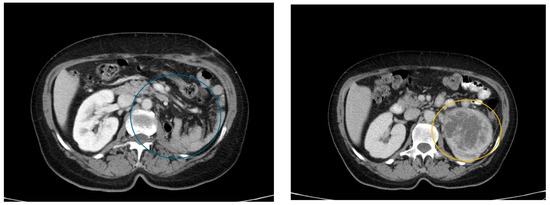

Following recommendations, one month later, she underwent a CT scan to complete diagnostic imaging (Figure 1). The scan showed a macronodular tumor in the left kidney, with dimensions of approximately 70/81/86 mm. The tumor appeared heterogeneous, with a predominantly peripheral, solid, and iodophilic component and a central, non-homogeneous, hypodense, and semi-solid component, located in the lower half of the anterior valve. The lesion exerted compressive effects on the pyelocaliceal system and renal pedicle, resulting in Grade II ureterohydronephrosis and the dilation of the ipsilateral renal vein, with extracapsular extension beyond the anterior perirenal fascia. Regional lumbar aortic lymph nodes with diameters up to 7/12 mm were also noted.

Figure 1.

CT scan revealing the tumor formation in the left kidney (marked in blue and yellow circles).